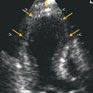

A regimen for treatment of acute coronary syndrome was started, including enoxaparin, a β-blocker, aspirin, a statin, and an angiotensin-converting enzyme (ACE) inhibitor. Cardiac catheterization revealed only minimal luminal irregularities in a right dominant coronary system. An echocardiogram showed normal left ventricular size and mass index with isolated apical dyskinesis (arrows) and an ejection fraction of 40% (B). The findings were consistent with apical ballooning syndrome.